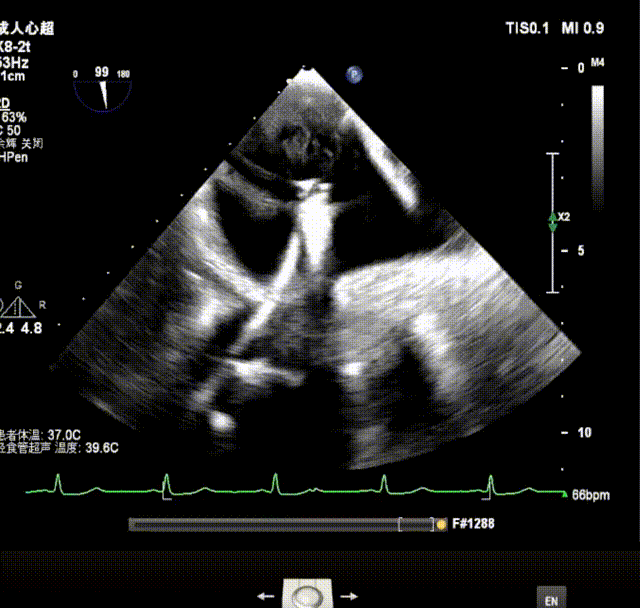

术前超声诊断:双房扩大,二三尖瓣中度关闭不全,二尖瓣P2P3偏P2区脱垂,主动脉瓣轻中度关闭不全,升主动脉增宽,TEER解剖难度分级:黄区,轻度肺高压。LVEF为73%。

X-plane视窗可见二尖瓣病变区脱垂,重度偏心性返流.

3D enface view示二尖瓣P2P3区瓣叶脱垂,偏心性返流